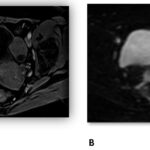

Se presenta el caso de una paciente de 56 años, posmenopáusica, con antecedente de Ca mama en tratamiento con anastrozol, anexectomía derecha por cistoadenoma seroso. Consulta por sangrado uterino anormal de un mes de evolución. Se realizan exámenes complementarios, como ecografía transvaginal y resonancia magnética pélvica, para evaluar la lesión; se categorizó como ORADS IV.

Anexos (imágenes)